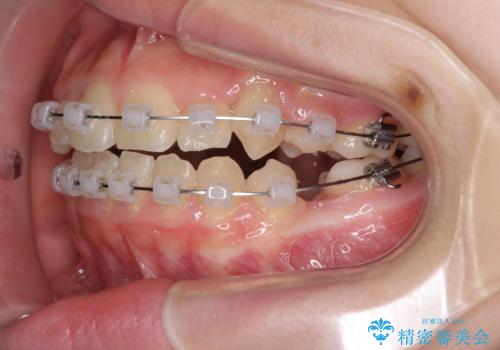

- クリアブラケット

- 2年1ヶ月

- 10-30回

下顎の乳歯は永久歯と比べて幅が大きいため、抜歯した場合のスペースが大きく、治療には長期間を要することが一般的です。

今回の患者様は中学生ということもあり、成人の患者様と比べ動きが速く、2年間で治療を終えることができました。